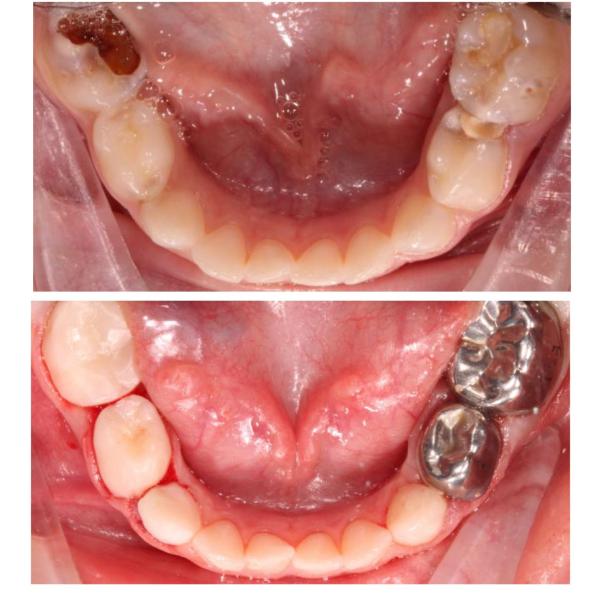

Пролечила 5-х детей в условиях медикаментозного сна, приняла около 10 ортодонтических консультаций

В общем пролечено за сегодня около 40 зубов 🐥